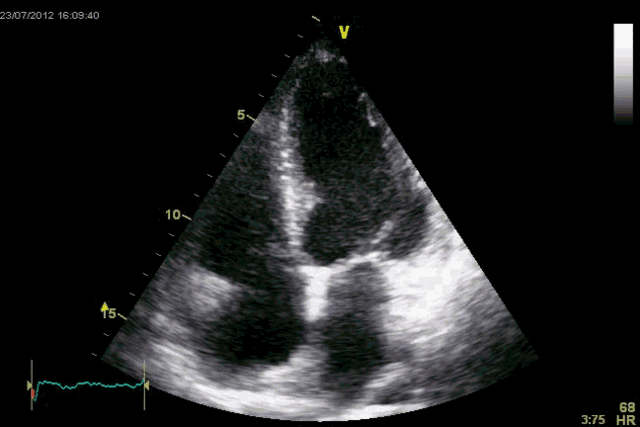

04超声下的心脏跳动图